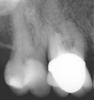

конфьюзд Опубликовано 15 мая, 2007 Поделиться Опубликовано 15 мая, 2007 По порядку: 1. тут я думаю все-таки врачу виднее, что можно было оставить, а что нельзя. в любом случае ему же было бы удобнее работать с зубом, е сли бы стенка была над десной. если спилил - значит так надо. нам во всяком случае судить не о чем. 2. запах строго говоря не показатель, хотя при хорошем охлаждении его наверно все же не должно ощущаться. 3.коффер хорошо конечно, но и без него можно обходиться. 4. а какой вы хотели запах почувствовать - перекись вообще не пахнет, спирт - на маленьком тампончике капля спирта вряд ли ударит Вам в нос. так что не переживайте. не вижу явных поводов для недоверия врачу. Другой вопрос что Вы чувствуете "непонятное"? Спасибо, Штаматолог. Хоть немножко меня успокоили. Что-то непонятное: было ощущение, что хочется все выковырять из зуба и почесать. Он тоже поставил пломбу возле коронки на 16, а на 17 вкладку. В 16-ом уже каналы нужно перелечить, но он почему-то не захотел это сейчас делать. Правая верхняя сторона уже беспокоит меня 2 месяца, а 5 июня артроскопия коленного сустава (подозревают я связку порвала), если б не это и на край света полетела б лечится. Снимок после лечения доктор не сделал, прилагаю снимок правой верхней части сделанный 17.04.2007. Ссылка на комментарий

Штаматолог Опубликовано 15 мая, 2007 Поделиться Опубликовано 15 мая, 2007 Спасибо, Штаматолог. Хоть немножко меня успокоили. Что-то непонятное: было ощущение, что хочется все выковырять из зуба и почесать. Он тоже поставил пломбу возле коронки на 16, а на 17 вкладку. В 16-ом уже каналы нужно перелечить, но он почему-то не захотел это сейчас делать. Правая верхняя сторона уже беспокоит меня 2 месяца, а 5 июня артроскопия коленного сустава (подозревают я связку порвала), если б не это и на край света полетела б лечится. Снимок после лечения доктор не сделал, прилагаю снимок правой верхней части сделанный 17.04.2007. Если почесать - скорее всего десна. Возможно как раз там, где полость уходит под десну. Либо просто задевали во время обработки и сейчас заживает, может конечно и вкладка сдавливает или излишки цемента например. Каналы 16 надо перелечивать. Почему Ваш доктор не посчитал нужным сделать это сейчас дляя меня не понятно. На 15 периодонтит. Между 15 и 14 пародонтит - явно виден карман на снимке. Ссылка на комментарий

конфьюзд Опубликовано 15 мая, 2007 Поделиться Опубликовано 15 мая, 2007 Если почесать - скорее всего десна. Возможно как раз там, где полость уходит под десну. Либо просто задевали во время обработки и сейчас заживает, может конечно и вкладка сдавливает или излишки цемента например. Возможно. Как Вы угадали? остатки цемента я сама удаляла Каналы 16 надо перелечивать. Почему Ваш доктор не посчитал нужным сделать это сейчас дляя меня не понятно. Согласна на все 100. Почему он не захотел - не знаю. Может он не умеет лечить сложные каналы На 15 периодонтит. Между 15 и 14 пародонтит - явно виден карман на снимке. Каналы 14 и 15 перелечил эндодонт в Октябре. Первый раз их лечили в советское время. А перед постановкой коронок просила троих стоматологов перелечить - не сумели или не захотели - не знаю. За эти годы возле корня 14-го выросла большая круглая косточка и возле 15-го поменьше, после лечения каналов косточка возле 15 рассасывается (может это на рентгене кажется периодонтитом?), а возле 14-го косточка не уменьшается. Согласна, что есть пародонтит между 14 и 15. На снимке (12 марта 2007), он выглядит получше (прилагаю этот снимок), не знаю или дело в качестве снимка или болезнь прогрессирует. Спасибо за участие, Штаматолог Ссылка на комментарий